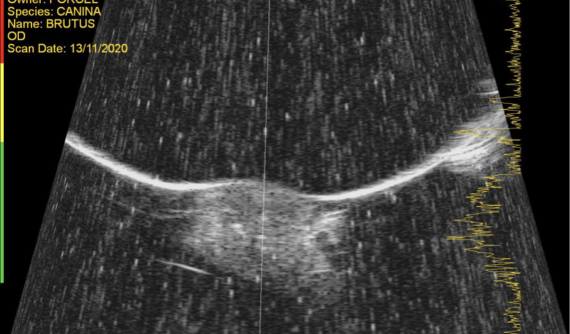

Tras la exploración oftalmológica completa realizamos una OCT de córnea y una ecografía UBM para valorar apropiadamente la masa y su profundidad.

El resultado de la biopsia fue de carcinoma de células escamosas in situ.